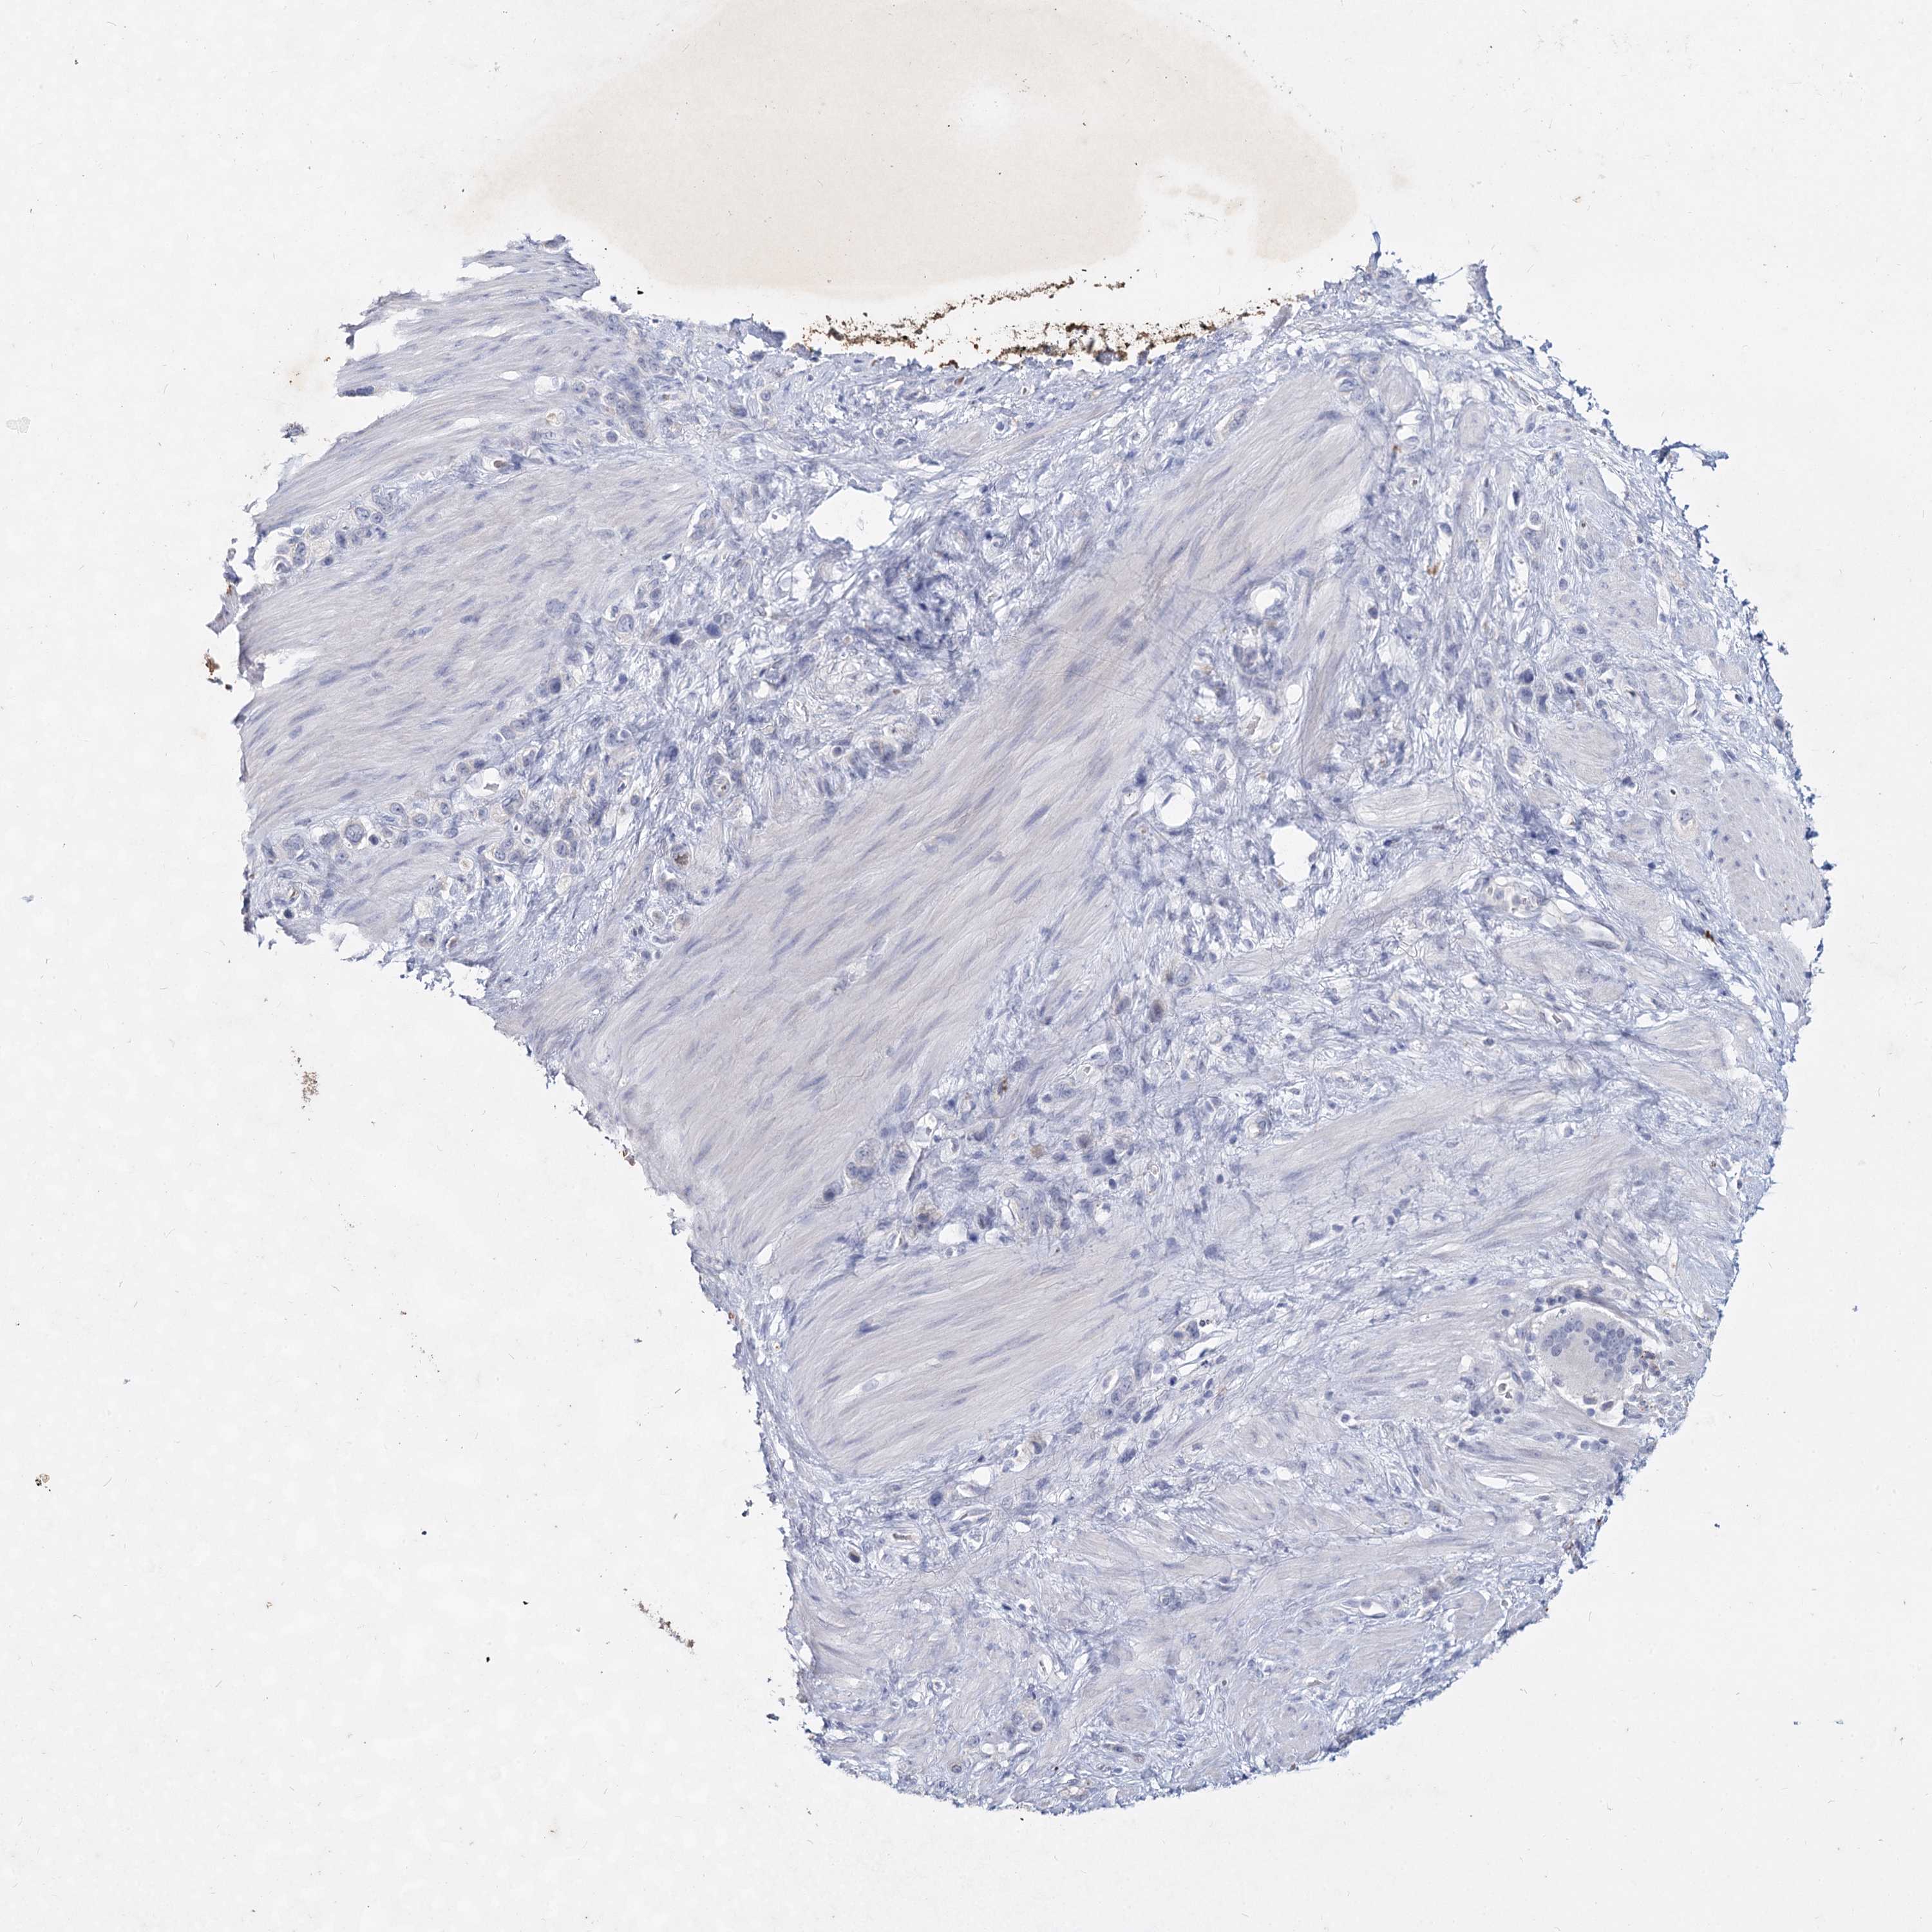

STOMACH CANCER - Protein expressioni

A mouse-over function shows sample information and annotation data. Click on an image to view it in a full screen mode. Samples can be filtered based on level of antibody staining by selecting one or several of the following categories: high, medium, low and not detected. The assay and annotation is described here.

Note that samples used for immunohistochemistry by the Human Protein Atlas do not correspond to samples in the TCGA dataset.

Antibody stainingi

Antibody staining in the annotated cell types in the current human tissue is reported as not detected, low, medium, or high, based on conventional immunohistochemistry profiling in selected tissues. This score is based on the combination of the staining intensity and fraction of stained cells.

Each image is clickable and will lead to virtual microscopy that enables deeper exploration of all samples and also displays staining intensity scores, fraction scores and subcellular localization as well as patient and tissue information for each sample.

Antibody HPA038668

Antibody HPA038669

Adenocarcinoma, NOS

Adenocarcinoma, High grade